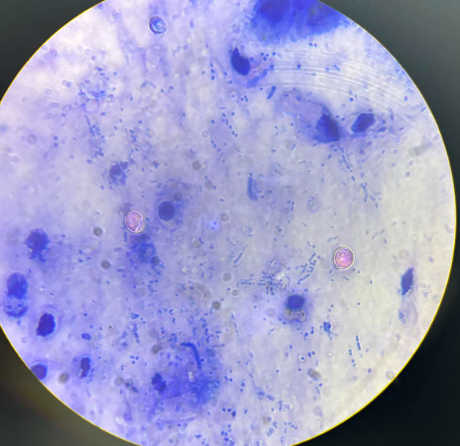

cryptosporidium parvum oocysty

cyclospora cayetanensis oocysty

cyclospora cayetanensis oocysty